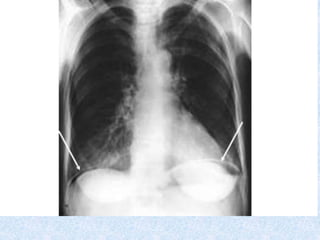

DIAGNOSIS: Clinical

• Supported by CXR

• hyperinflation, flat diaphragm, air bronchograms,

peribronchial cuffing, patchy infiltrates, atelectasis

Air trapping. Peribronchial cuffing due to wall thickening. Minimal

focal atelectasis. Tubular heart. Flat low-set D

Peribronchial

cuffing

CXR: hyperinflation withflattened diaphragm & bilateral atelectasis in the R apical & L basal regions in a 16d-old with severe bronchiolitis